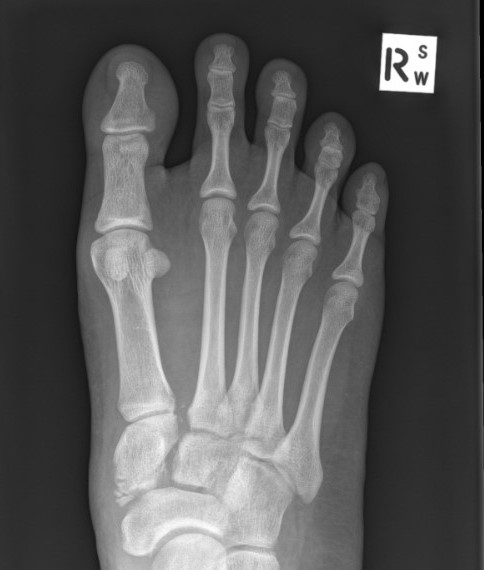

X-ray

Subtle widening of the medial cuneiform - 2nd metarsal distance, and the inter-metatarsal distance